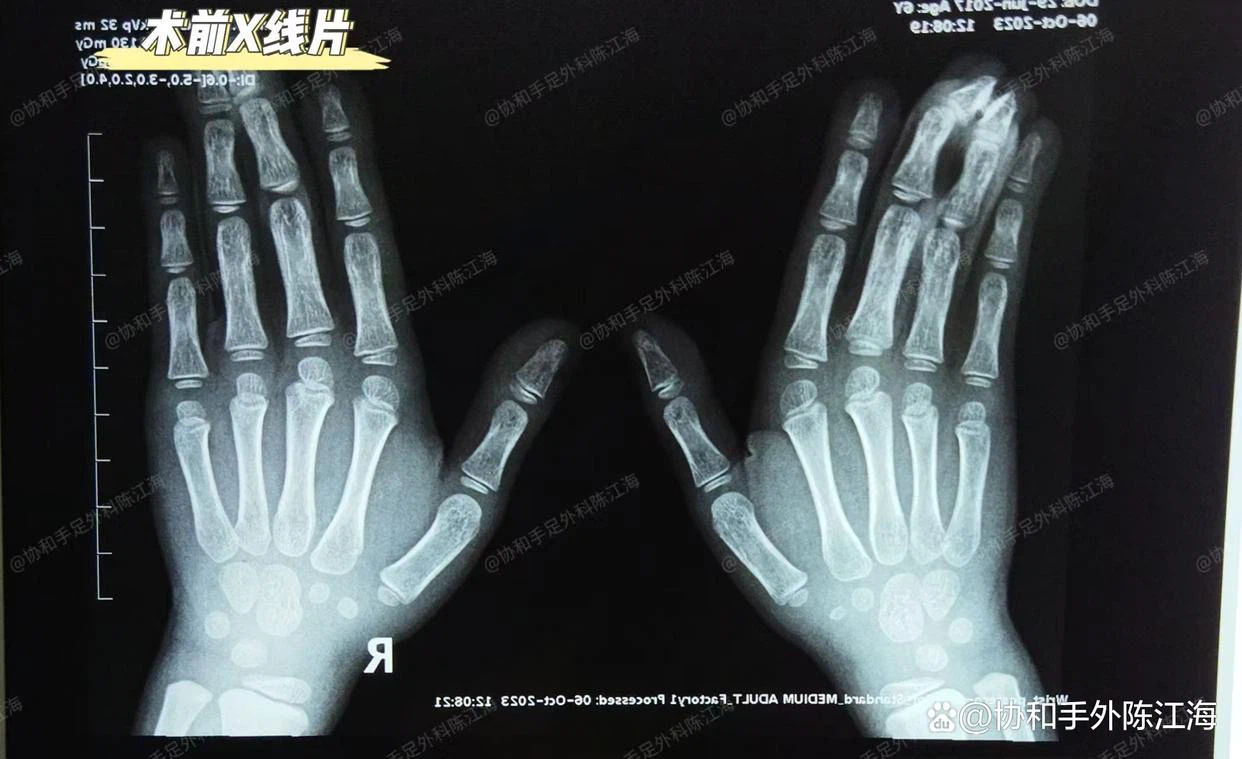

Radiografie pre-chirurgie